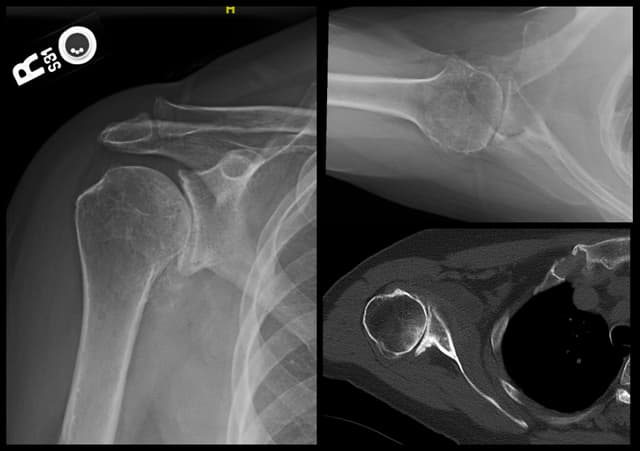

Imaging